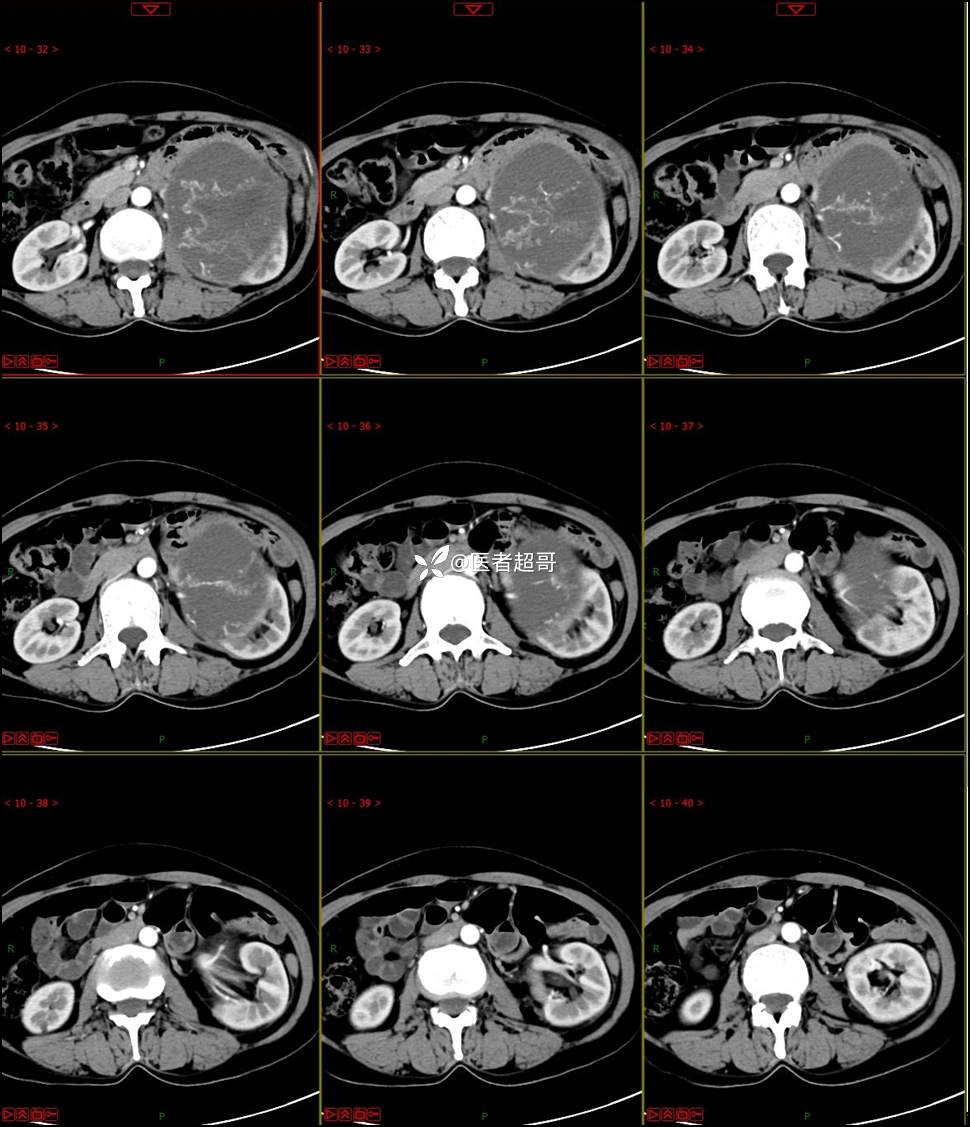

【影诊笔记768】肾脏肿瘤?肾上腺肿瘤?请诊断分析!

女 57岁 0200908 01

主 诉:发现左肾肿物7月余

现病史:患者7月前因左侧腹部疼痛不适,就诊市人民医院,行CT平扫:左侧肾上腺区混杂密度肿块,考虑肿瘤合并出血,行保守治疗后症状缓解出院,左侧下腹部及左侧髋部疼痛不适,无尿频、尿急、尿痛,无肉眼血尿,无寒战、发热,今患者为求进一步诊治,就诊我院,门诊以“左肾肿物”为诊断收入院,患者自发病以来,神志清,精神可,饮食睡眠可,小便如上述,大便正常,体重未见明显改变。